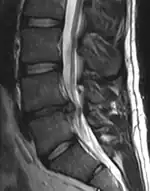

Imaging is indicated when there are red flags, ongoing neurological symptoms that do not resolve, or ongoing or worsening pain.[5] In particular, early use of imaging (either MRI or CT) is recommended for suspected cancer, infection, or cauda equina syndrome.[5] MRI is slightly better than CT for identifying disc disease; the two technologies are equally useful for diagnosing spinal stenosis.[5] Only a few physical diagnostic tests are helpful.[5] The straight leg raise test is almost always positive in those with disc herniation,[5] and lumbar provocative discography may be useful to identify a specific disc causing pain in those with chronic high levels of low back pain.[44] Therapeutic procedures such as nerve blocks can also be used to determine a specific source of pain.[5] Some evidence supports the use of facet joint injections, transforminal epidural injections and sacroiliac injections as diagnostic tests.[5] Most other physical tests, such as evaluating for scoliosis, muscle weakness or wasting, and impaired reflexes, are of little use.[5]

Complaints of low back pain are one of the most common reasons people visit doctors.[45][46] For pain that has lasted only a few weeks, the pain is likely to subside on its own.[47] Thus, if a person's medical history and physical examination do not suggest a specific disease as the cause, medical societies advise against imaging tests such as X-rays, CT scans, and MRIs.[46] Individuals may want such tests but, unless red flags are present,[48][49] they are unnecessary health care.[45][47] Routine imaging increases costs, is associated with higher rates of surgery with no overall benefit,[50][51] and the radiation used may be harmful to one's health.[50] Fewer than 1% of imaging tests identify the cause of the problem.[45] Imaging may also detect harmless abnormalities, encouraging people to request further unnecessary testing or to worry.[45] Even so, MRI scans of the lumbar region increased by more than 300% among United States Medicare beneficiaries from 1994 to 2006.[10]